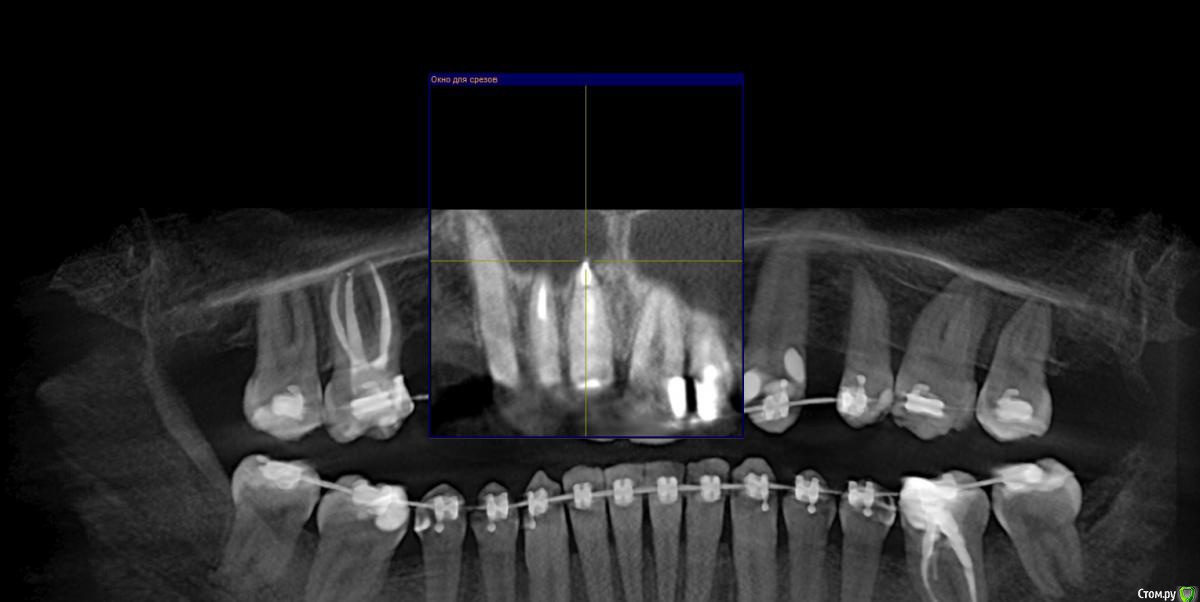

Al..ks Опубликовано 18 апреля, 2019 Поделиться Опубликовано 18 апреля, 2019 Добрый день. Планируется имплантация(15 или 14. брекеты ношу, поэтому не знаю какой будет)+аугментация (в области кармана 17 и при имплантации в случае недостатка кости)+пластика десны+установка формирователя. Все за раз.На выбор dentium, Astra, Nobel, Straumann. Подходят любые и выбор за мной(я склоняюсь к Астре). Правильный выбор? . Плюс ко всему по КТ там отсутствует кортикальный слой( по словам врача) я так понял с наружней стороны, поможет ли аугментация?И поможет ли она с карманом 17? И так как двигали зубы в области корня 11 появилась пустота (толи уже было)в середине лечения и на данный момент Надо ли делать резекцию корня - или канал перелечивать (там ставили СВШ перед брекетами) перед протезирование? Ссылка на комментарий

suballex Опубликовано 19 апреля, 2019 Поделиться Опубликовано 19 апреля, 2019 Добрый день. Планируется имплантация(15 или 14. брекеты ношу, поэтому не знаю какой будет)+аугментация (в области кармана 17 и при имплантации в случае недостатка кости)+пластика десны+установка формирователя. Все за раз.На выбор dentium, Astra, Nobel, Straumann. Подходят любые и выбор за мной(я склоняюсь к Астре). Правильный выбор?Правильный Плюс ко всему по КТ там отсутствует кортикальный слой( по словам врача) я так понял с наружней стороны, поможет ли аугментация?И поможет ли она с карманом 17?Аугментация с карманом не поможет. В остальном - да И так как двигали зубы в области корня 11 появилась пустота (толи уже было)в середине леченияи на данный момент Надо ли делать резекцию корня - или канал перелечивать (там ставили СВШ перед брекетами) перед протезирование?Нужно сравнить КТ начала лечения и последнее. Рентгенологически, канал 11 пролечен хорошо. Возможно, это остаточные явления. Ссылка на комментарий